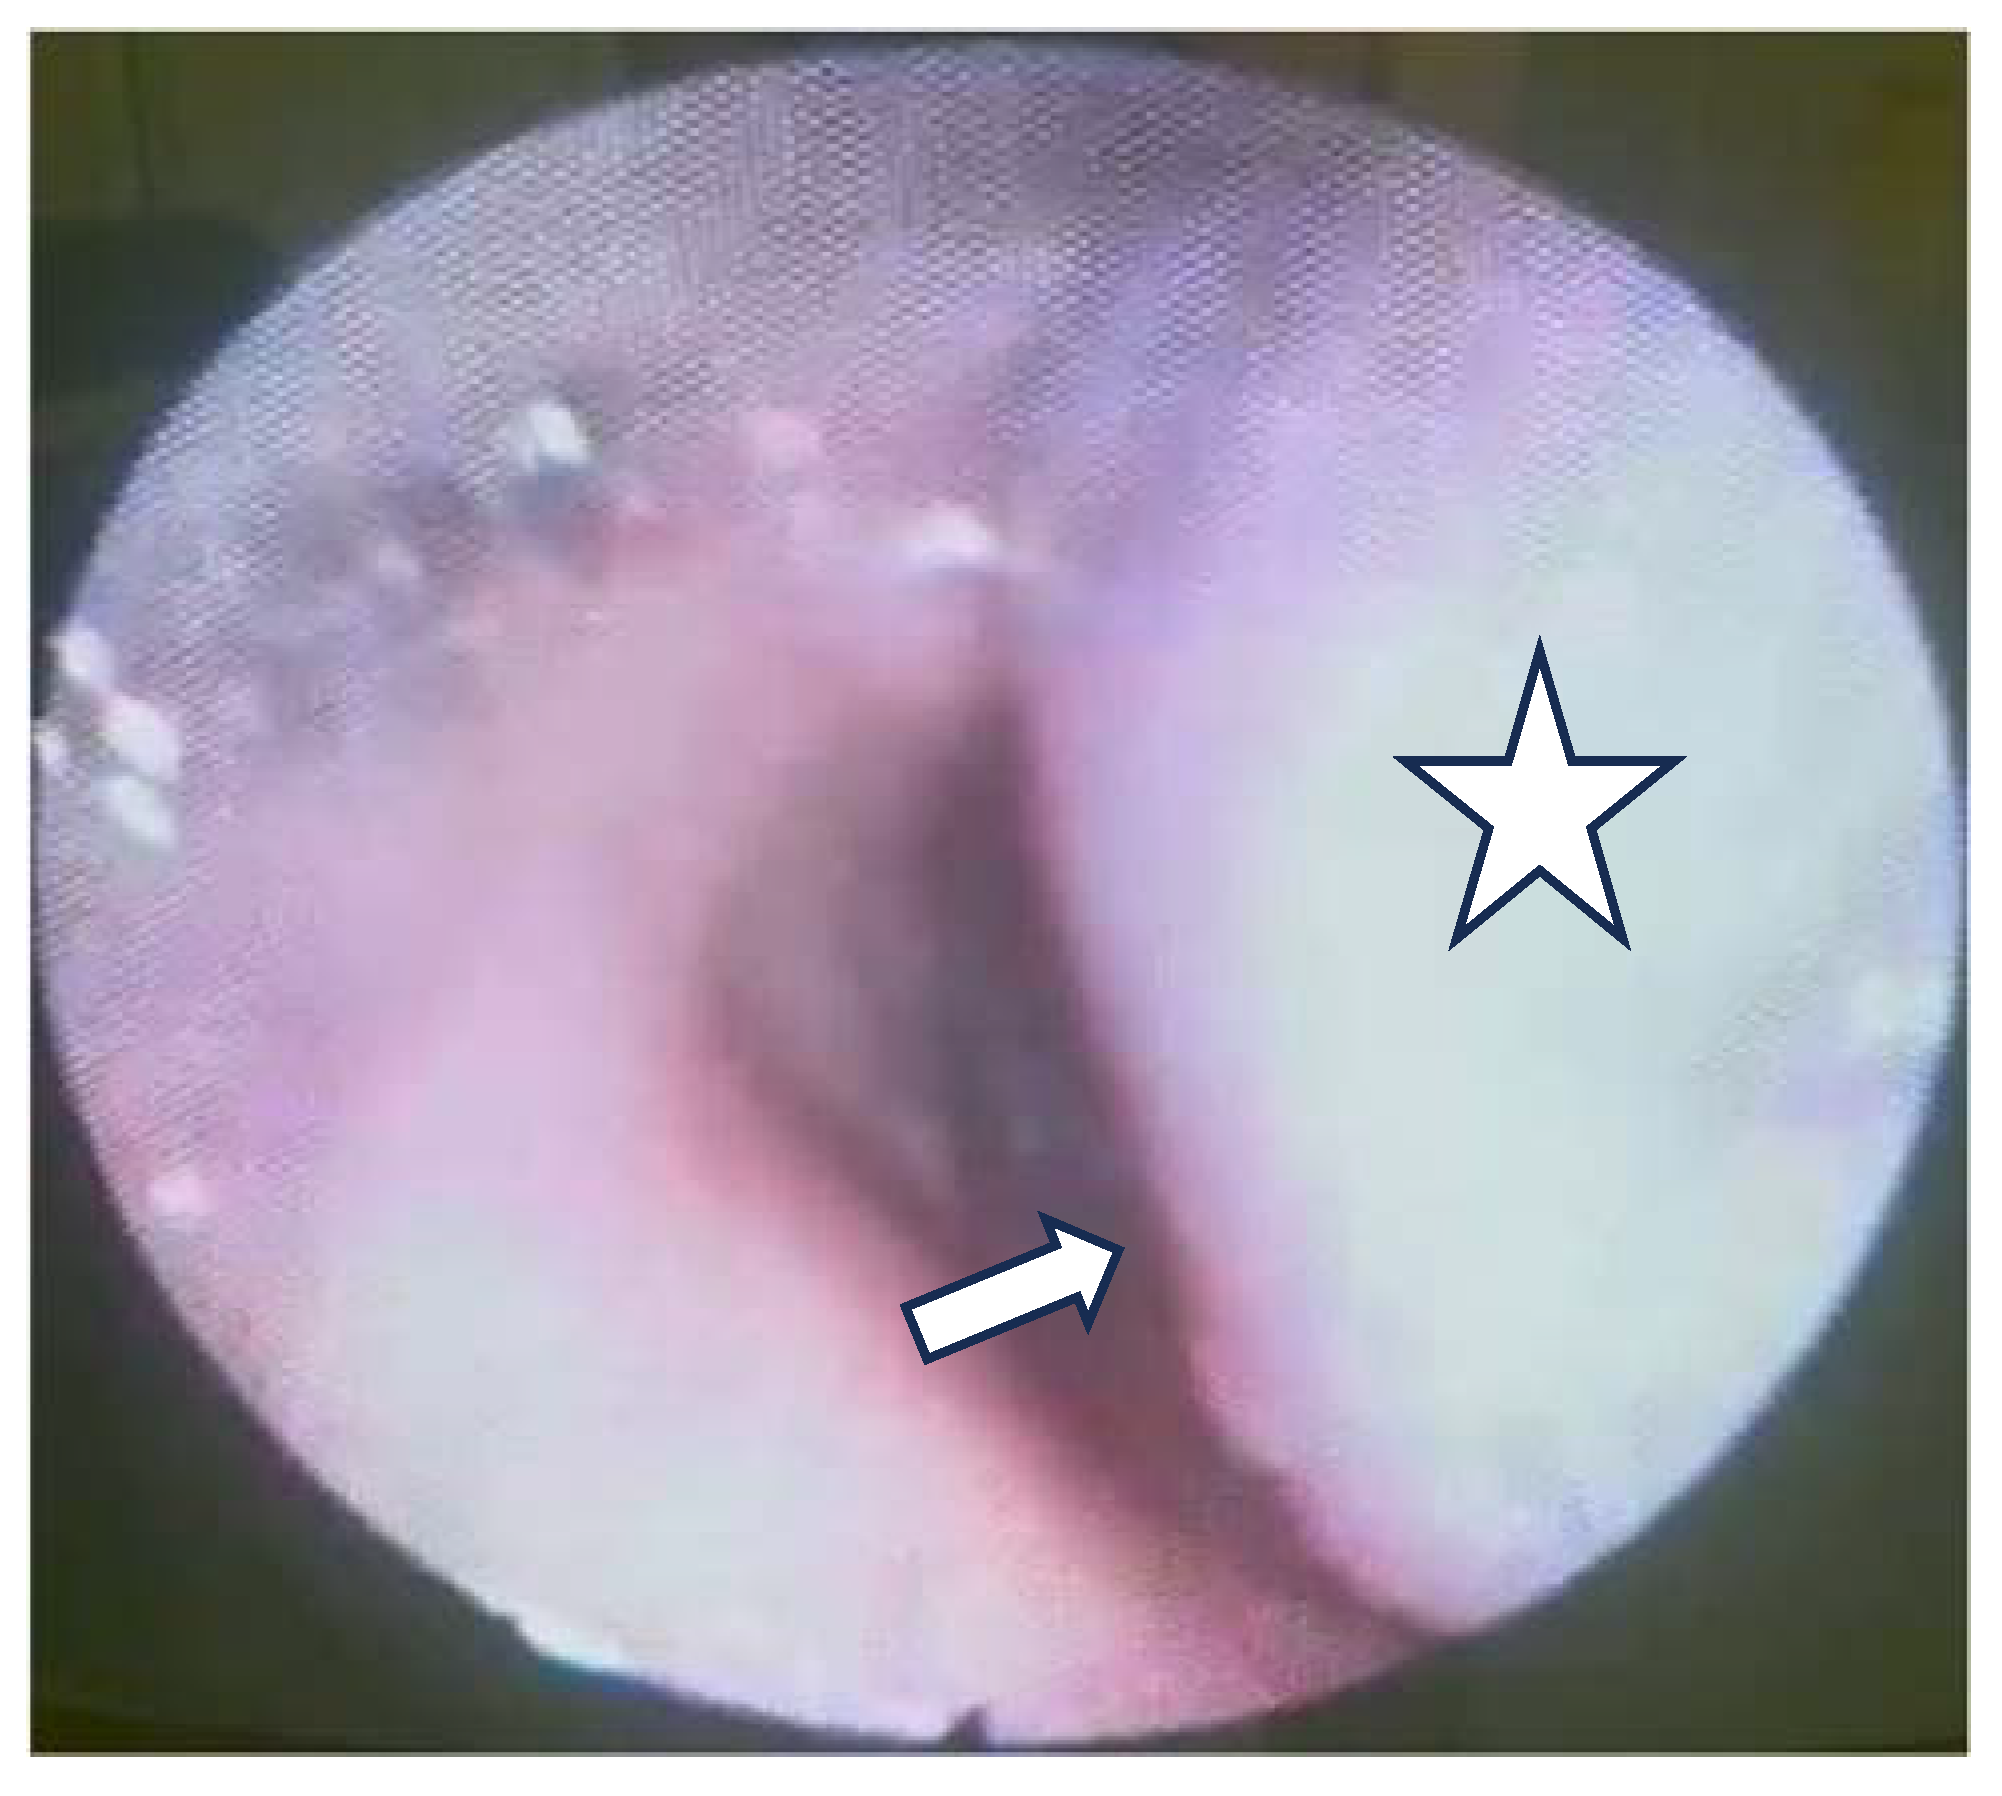

The flexible video laryngoscopy examination revealed a supraglottic mass covering the left aryepiglottic fold and the left arytenoid cartilage, extending to the ipsilateral pyriform sinus. The tumor presented a pronounced vascular draw, having a blueish color. The tumor deviated from the left hemilarynx medially, thus decreasing the movement of the left true vocal fold. The tumor tilted over the laryngeal inlet’s opening, causing breathing difficulties. The right vocal fold has a normal aspect, with normal movement, while the tumor did not obstruct the glottic space (Figure 1).

Figure 1.

The tumor bulges into the laryngeal inlet (the laryngeal inlet is marked by the arrow and the tumor by a star).